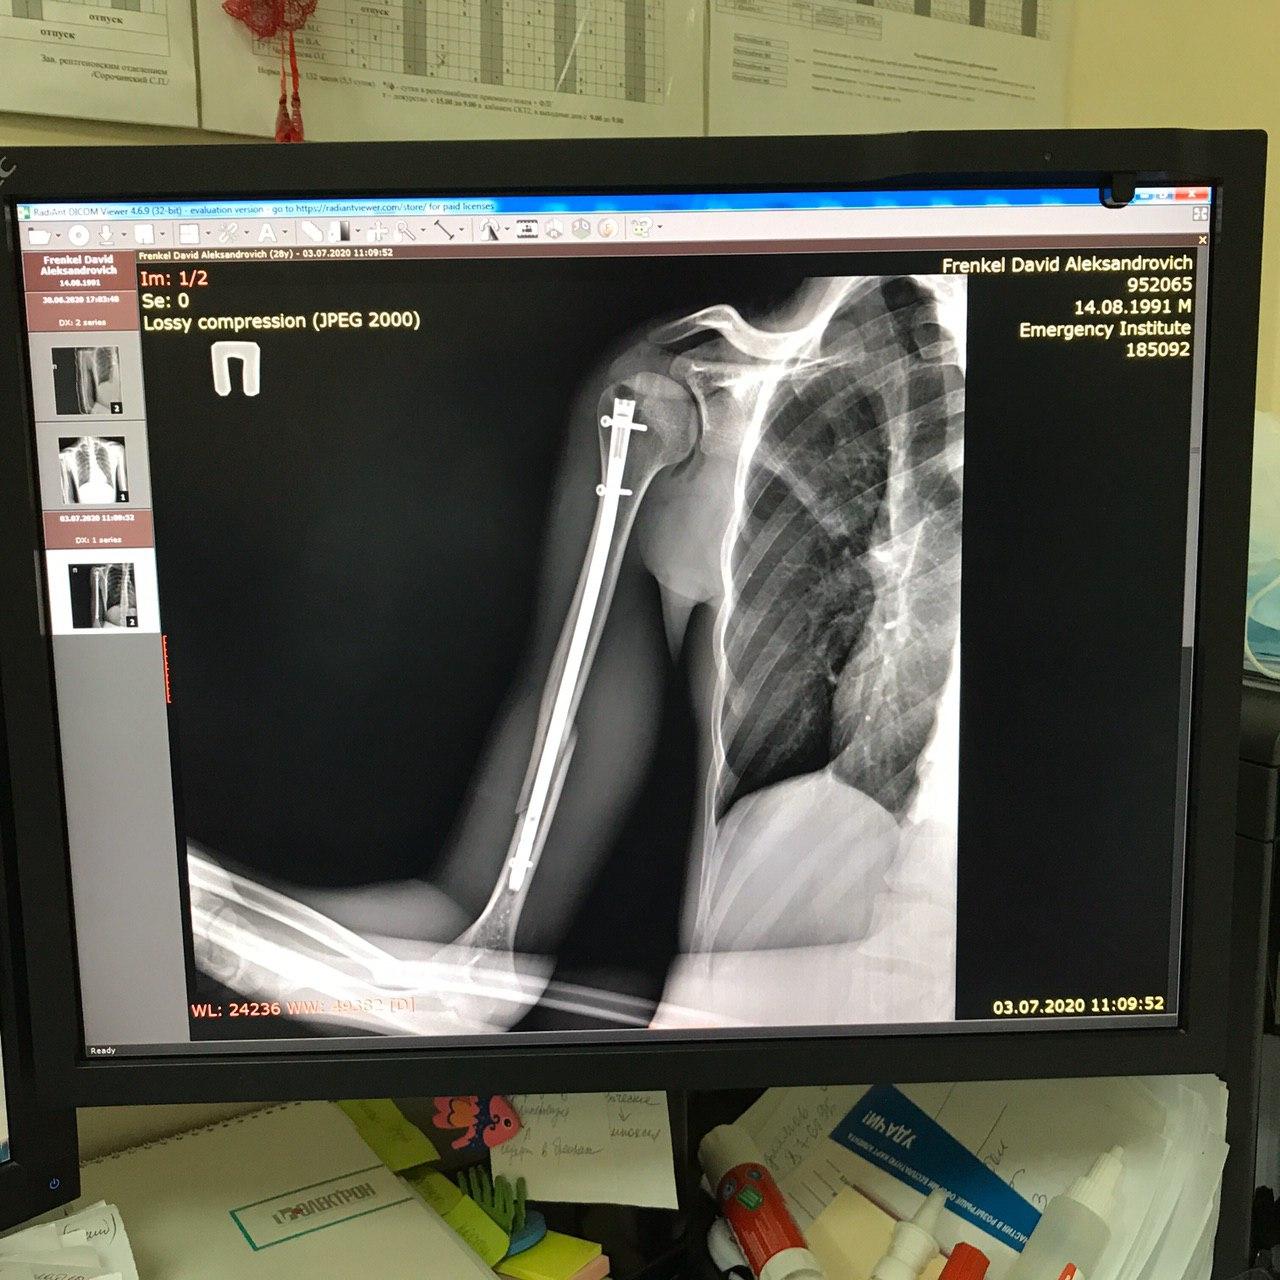

Френкеля госпитализировали в НИИ имени Джанелидзе в день нападения. Операция длилась четыре часа, пострадавшему вставили в предплечье интрамедуллярный стержень. Только спустя неделю после госпитализации он получил медицинские документы. Согласно заключительному диагнозу, у журналиста зафиксировали закрытый перелом средней трети правой плечевой кости со смещением.

Фото рентгена руки Давида Френкеля после операции / Фото: адвокат Ольга Карачева